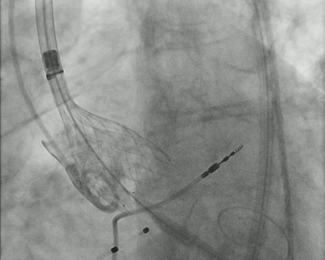

A 33-year-old man with Behçet's disease presented with new retrosternal chest pain and was transferred for primary percutaneous coronary intervention due to inferior ST-segment elevation myocardial infarction.